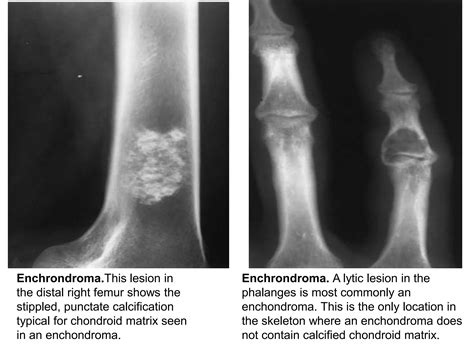

At its core, a lytic lesion is a focal area within the bone structure where mineral density has been significantly reduced. This reduction creates "holes" or voids in the bone, which are easily identified on X-rays as darker, radiolucent patches. The process is usually driven by the activation of osteoclasts—the cells responsible for breaking down bone tissue. When pathological processes, such as the invasion of metastatic cancer cells or inflammatory cytokines, trigger these cells, they erode the bone matrix prematurely.

To determine the etiology of Lytic Skeletal Lesions, radiologists and physicians utilize various imaging modalities, including plain radiographs, computed tomography (CT), magnetic resonance imaging (MRI), and positron emission tomography (PET) scans. Each modality offers different insights into the borders, matrix, and surrounding soft tissue involvement of the lesion.

Effective management of Lytic Skeletal Lesions relies on a systematic imaging protocol. A plain radiograph is almost always the initial step. If the lesion has a sclerotic rim, it may suggest a slow-growing, benign process. Conversely, an ill-defined or "moth-eaten" appearance usually mandates immediate follow-up with more sophisticated imaging like an MRI to assess the extent of the marrow infiltration and soft tissue involvement.